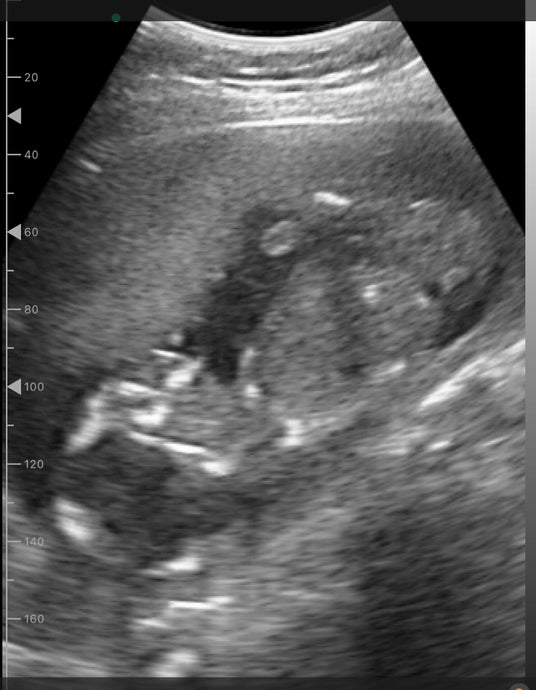

ポケマムで見た胎児の様子